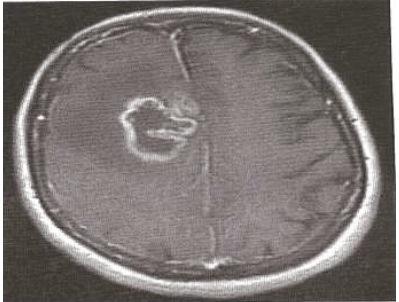

Paciente, sexo masculino, realizou uma ressonância magnética de encéfalo, mostrada na figura abaixo, e o exame histopatológico demonstra neoplasia glial com necrose e hiperplasia endotelial.

RM axial ponderada em T1 pôs-contraste.